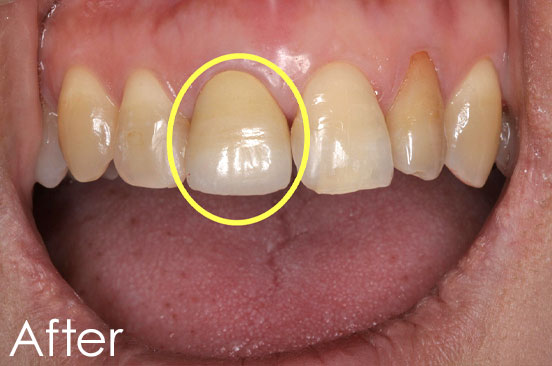

女性Jさん(10代学生)

お悩み:差し歯の見た目と歯の色と歯茎の色が気になる。

治療内容:歯ぐきの着色に対するレーザー治療、歯の黄ばみに対するホワイトニング、保険の差し歯をジルコニアセラミッククラウンへのやりかえの治療

治療期間:約1ヶ月

治療回数:2回

金額:歯ぐきの着色に対するレーザー治療 11,000円(税込)

セラミック治療 134,000円(税込)

オフィスホワイトニング 49,500円(税込)

リスク・副作用:レーザー治療後、痛みがでることがあります。

ホワイトニング後はしみる可能性があります。

レーザーによるガムピーリングの特徴:レーザーを照射した歯肉は白濁し、2,3日程で剥がれ落ちて、ピンク色の新しい歯肉があらわれます。